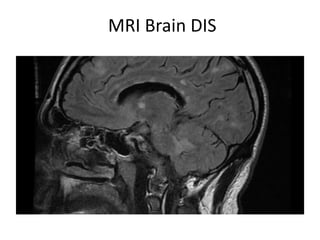

MRI Brain DIS

Dissemination in Space

Polman CH et al, Ann Neurol 2011; 69:292–302